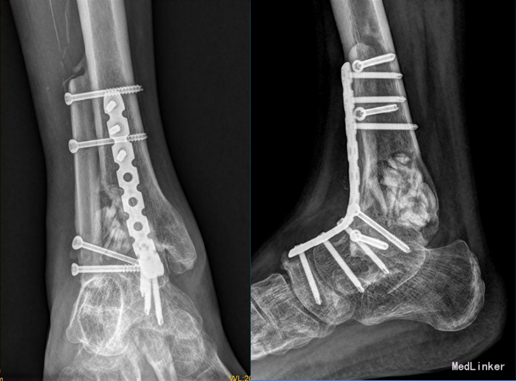

1年后患者行右踝关节肿物切除+踝关节融合取腓骨重建术。